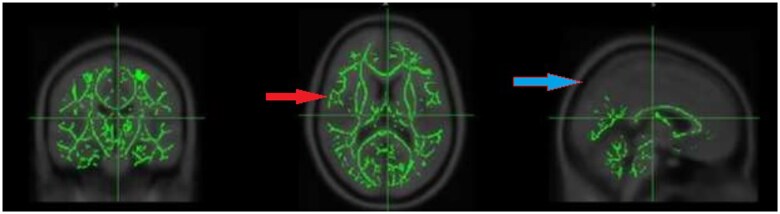

Methods: A prospective cohort analysis was conducted comprised 60 RA patients with fatigue, categorized into active (n = 30) and non-active (n = 30) disease states, alongside 20 healthy controls (HC). A 3 Tesla MRI system was utilized to perform diffusion tensor imaging (DTI) and magnetization transfer imaging (MTI) sequences. MTR maps were generated using in-house MATLAB code and co-registered with DTI data using SPM8. These were then analyzed through tract-based spatial statistics (TBSS) with threshold-free cluster enhancement (TFCE) and corrected for multiple comparisons. MTR values were assessed using Randomize from the FSL toolkit, applying a general linear model (GLM) for voxel-wise analysis and TFCE for p-value generation, with family-wise error (FWE) control (P < .05) for multiple comparisons.

Results: The RF group exhibited significantly lower myelin integrity (TFCE, P < .05) compared to HCs, particularly in the middle cerebellar peduncle and splenium of the corpus callosum, with no marked difference between active and non-active RA disease statuses. There is a discernible disparity in myelin integrity between RA patients with fatigue and healthy individuals, suggesting microstructural white matter alterations that are congruent with DTI findings.

Conclusion: This study reveals that rheumatoid arthritis (RA) patients with fatigue exhibit significantly lower myelin integrity, particularly in the middle cerebellar peduncle and splenium of the corpus callosum, compared to healthy controls. Notably, this finding was consistent regardless of the active or non-active status of the RA disease, highlighting persistent white matter alterations in this patents cohort.